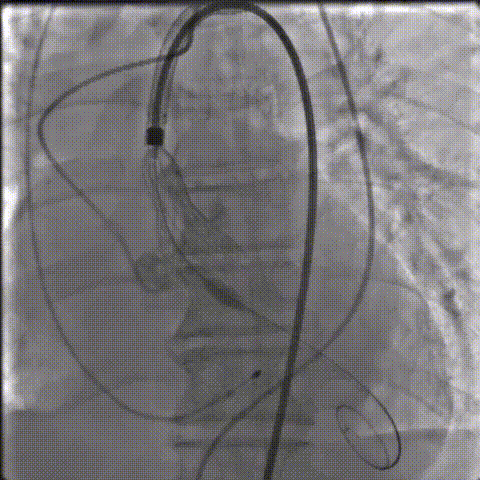

手术影像记录

缓慢脱钩

23mm球囊后扩

后扩后造影:无漏

超声评估

超声多切面评估,血流动力学改善明显,无瓣周漏